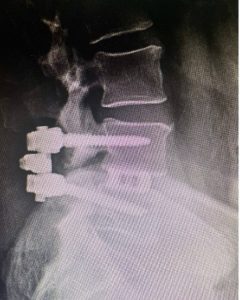

Image 2: The X-rays revealed that he had severe spinal stenosis as the L4 and L5 as well as spondylolisthesis, which caused instability.